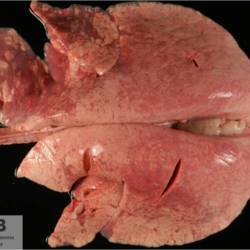

Pàgina anterior de 637 Pàgina següent 3181 total Ovine Specie: Ovine Organ: Brain Lesion: Necrosis Lesion modifier: - Disease: Polioencephalomalacia of ruminants Files/Expedient: Leon3 Position: 253 (1 views) Ovine Specie: Ovine Organ: Brain Lesion: Malacia Lesion modifier: - Disease: Polioencephalomalacia of ruminants Files/Expedient: Leon3 Not viewed Ovine Specie: Ovine Organ: Lung Lesion: Pneumonia Lesion modifier: Pneumonia - Interstitial - Chronic Disease: Maedi-visna Position: 253 (1 views) Ovine Specie: Ovine Organ: Intestine Lesion: Enteritis Lesion modifier: Enteritis - Granulomatous Disease: Paratuberculosis Position: 253 (1 views) Ovine Specie: Ovine Organ: Brain Lesion: Meningocele Lesion modifier: - Disease: - Files/Expedient: Leon2 Not viewed Pàgina anterior de 637 Pàgina següent Títol Select...Avian (Exotic) (110)Avian (Poultry) (76)Bovine (317)Canine (935)Caprine (47)Equine (257)Feline (326)Ferret (19)General (127)Marine mammal (22)Non-human primate (20)Ovine (328)Porcine (379)Rabbit (61)Reptile (38)Rodent (28)Wildlife (91) Format Select...- (60)Abomasum (37)Adrenal gland (10)Blood (7)Blood vessel (50)Body as a whole (19)Bone (57)Bone marrow (21)Brain (93)Cloaca (1)Diaphragm (2)Ear (5)Esophagus (39)Eye (16)Fetus (12)Gallbladder (23)Gizzard (2)Heart (265)Intestine (356)Joint (32)Kidney (443)Larynx (5)Liver (326)Lung (264)Lymph node (91)Mammary gland (10)Mediastinum (1)Muscle (22)Nasal cavity (22)Nerve (7)Omasum (5)Oral cavity (63)Ovary (14)Oviduct (8)Pancreas (7)Parathyroid (5)Penis (10)Peritoneum (65)Pharynx (9)Pituitary gland (6)Placenta (7)Prostate (8)Proventriculus (3)Reticulum (1)Rumen (28)Sinus (7)Skin (181)Spinal cord (15)Spleen (105)Stomach (125)Teeth (1)Testicle (11)Thoracic cavity (31)Thymus (13)Thyroid gland (5)Tongue (32)Tonsils (11)Trachea (11)Urethra (5)Urinay bladder (61)Uterus (27)Vagina (1)Vulva (1)Yolk sac (1) Cobertura Select...- (152)Abomasitis (26)Abscess (27)Acidosis (1)Adenocarcinoma (20)Adenoma (9)Aerosacculitis (6)Agenesis (1)Agnathia (1)Alopecia (7)Amyloidosis (12)Aneurysm (6)Angiectasis (1)Anthracosis (1)Arteritis (11)Arthritis (15)Arthrogryposis (6)Artifact (4)Ascites (13)Atelectasis (8)Atherosclerosis (5)Atresia (1)Atrial septal defect (2)Atrophy (10)Autolysis (7)Bronchitis (6)Bronchopneumonia (26)Cachexia (2)Carcinoma (103)Cardiomyopathy (19)Cellulitis (2)Chemodectoma (4)Cholangiohepatitis (4)Cholangitis (19)Cholecystitis (4)Cholestasis (5)Chondrodysplasia (2)Chondrosarcoma (2)Chronic passive congestion (13)Chylothorax (2)Cirrhosis (6)Coelomitis (3)Coenurus cerebralis (4)Colitis (40)Congestion (17)Conjunctivitis (5)Coronitis (3)Cryptorchidism (3)Cyst (25)Cystitis (24)Dermatitis (69)Diaphragmatic hernia (4)Dilation (28)Discospondylitis (1)Disseminated intravascular coagulation (7)Dyschondroplasia (1)Dysplasia (29)Ectopia cordis (1)Ectopic ureter (1)Edema (55)Emphysema (5)Encephalitis (5)Endocardiosis (14)Endocarditis (26)Endometritis (5)Enteritis (118)Enterolith (6)Epulis (3)Esophagitis (14)Fasciitis (1)Fibrosis (7)Fibrous osteodystrophy (8)Fistula (1)Folliculitis (3)Fracture (2)Gastritis (34)Gingivitis (5)Glioma (8)Glomerulonephritis (21)Glossitis (25)Glycogenosis (1)Gout (8)Granuloma (2)Granulosa cell tumor (4)Hemangioma (9)Hemangiosarcoma (46)Hematoma (8)Hemoglobinuria (2)Hemopericardium (12)Hemoperitoneum (2)Hemorrhage (100)Hemosiderosis (7)Hemothorax (2)Hepatitis (78)Hernia (11)Histiocytosis (3)Hydatid cyst (11)Hydrocephalus (9)Hydrometra (1)Hydronephrosis (22)Hydropericardium (6)Hydrothorax (3)Hydroureter (5)Hyperkeratosis (8)Hyperostosis (4)Hyperplasia (37)Hypertrophy (9)Hypopigmentation (1)Hypoplasia (7)Hypopyon (1)Impaction (6)Infarction (63)Insulinoma (6)Intussusception (5)Jaundice (17)Laminitis (2)Laryngitis (2)Leiomyoma (5)Leukemia (13)Lipidosis (36)Lipoma (7)Lymphadenitis (45)Lymphadenopathy (7)Lymphangiectasia (6)Lymphangitis (5)Lymphoma (221)Malacia (11)Malignant melanoma (15)Mast cell tumor (11)Mastitis (8)Megaesophagus (2)Melanosis (3)Melena (4)Meningioma (6)Meningitis (6)Meningocele (2)Meningoencephalitis (5)Mesothelioma (5)Methemoglobinemia (2)Mineralization (10)Mucocele (5)Mucometra (1)Multilobular bone tumor (1)Mummification (3)Myelofibrosis (1)Myocarditis (4)Myositis (5)Necrosis (81)Nephritis (113)Nephroblastoma (6)Nephrosclerosis (1)Nephrosis (14)Neuritis (1)Obstruction (13)Omasitis (4)Omphalitis (1)Omphalophlebitis (7)Orchitis (4)Osteoarthrosis (5)Osteomyelitis (9)Otitis (2)Palatoschisis (3)Pancreatitis (3)Panniculitis (3)Papilloma (7)Parakeratosis (14)Patent ductus arteriosus (6)Peliosis hepatis (1)Perforation (17)Pericarditis (35)Peritonitis (39)Persistent right aortic arch (1)Pharyngitis (2)Pheochromocytoma (2)Phlebitis (2)Placentitis (6)Pleuritis (21)Pleuropneumonia (24)Pneumonia (109)Pneumothorax (3)Polycystosis (14)Polyp (5)Polyserositis (6)Posthitis (1)Proctitis (4)Prolapse (3)Prostatitis (3)Proventriculitis (1)Pyelonephritis (24)Pyometra (6)Pyothorax (4)Rhinitis (11)Rumenitis (6)Rupture (24)Salpingitis (3)Sarcoma (57)Sclerosis (1)Scoliosis (2)Seminoma (2)Sequestrum (2)Serous atrophy (14)Sinusitis (7)Splenitis (14)Splenomegaly (9)Spondylitis (6)Spondylosis (1)Stenosis (9)Stomatitis (32)Tenosynovitis (2)Teratoma (3)Thricobezoar (2)Thrombosis (16)Tonsilitis (4)Torsion (13)Tracheitis (4)Tympany (7)Typhlitis (8)Typhlocolitis (4)Ulcer (43)Urethritis (1)Urolithiasis (36)Uroperitoneum (1)Uveitis (1)Vasculitis (15)Ventricular septal defect (3)Volvulus (11) Matèria Select... - (14)- (1653)- (152)Abomasitis - Catarrhal (2)Abomasitis - Catarrhal-hemorrhagic (1)Abomasitis - Chronic (1)Abomasitis - Fibrinous-necrotizing (2)Abomasitis - Hyperplasic (5)Abomasitis - Hyperplasic - Chronic (1)Abomasitis - Necrotic (1)Abomasitis - Necrotizing (2)Abomasitis - Ulcerative (5)Adenocarcinoma (9)Aerosacculitis - Granulomatous (1)Amyloidosis - Chronic (1)Arteritis - Necrotic (2)Arteritis - Necrotizing (1)Arthritis - Chronic (4)Arthritis - Fibrinous-purulent (3)Arthritis - Serous (4)Arthritis - Subacute (1)Ascites - Serous (1)Atrophy - Serous (1)Bronchitis - Catarrhal (3)Bronchitis - Suppurative (1)Bronchopneumonia - Catarrhal-purulent (17)Bronchopneumonia - Fibrinous (1)Bronchopneumonia - Granulomatous (1)Bronchopneumonia - Purulent (1)Bronchopneumonia - Suppurative (5)Carcinoma - Adenocarcinoma (33)Carcinoma - Adenocarcinoma - Hepatocellular (2)Carcinoma - Adenocarcinoma - Mucinous (1)Carcinoma - Basosquamous (1)Carcinoma - Cholangiocellular (3)Carcinoma - Hepatocellular (4)Carcinoma - Metastatic (3)Carcinoma - Squamous cell carcinoma (13)Carcinoma - Transitional cell (2)Cardiomyopathy - Dilated (13)Cardiomyopathy - Hypertrophic (6)Cellulitis - Necrotizing (1)Cholangitis - Chronic (8)Cholangitis - Hyperplasic (3)Cholecystitis - Fibrinous-necrotizing (1)Coelomitis - Fibrinous (1)Coelomitis - Granulomatous (1)Colitis - Catarrhal (3)Colitis - Catarrhal-hemorrhagic (1)Colitis - Fibrinous (1)Colitis - Fibrinous-necrotizing (1)Colitis - Fibrinous-necrotizing (Diphtheritic) (6)Colitis - Granulomatous (2)Colitis - Hemorrhagic (4)Colitis - Hemorrhagic-necrotizing (3)Colitis - Necrotizing (2)Colitis - Ulcerative (6)Congestion - Chronic (2)Conjunctivitis - Hyperplasic (1)Conjunctivitis - Purulent (3)Coronitis - Ulcerative (1)Cystitis - Chronic (3)Cystitis - Fibrinous (1)Cystitis - Fibrinous-necrotizing (1)Cystitis - Follicular (1)Cystitis - Hemorrhagic (6)Cystitis - Hemorrhagic-ulcerative (1)Cystitis - Necrotizing (9)Cystitis - Perforated (1)Dermatitis - Granulomatous (14)Dermatitis - Hyperkeratotic (10)Dermatitis - Hyperplasic (proliferative) (1)Dermatitis - Hyperplastic (10)Dermatitis - Necrotizing (4)Dermatitis - Pustular (4)Dermatitis - Ulcerative (2)Dilation - Chronic (1)Discospondylitis - Necrotizing (1)Dysplasia - Follicular (5)Edema - Interstitial (6)Emphysema - Interstitial (1)Encephalitis - Granulomatous (1)Encephalitis - Nonsuppurative (1)Endocardiosis - Mitral (7)Endocardiosis - Mitral - Chronic (5)Endocarditis - Valvular (6)Endocarditis - Valvular - Mitral (7)Endocarditis - Valvular - Pulmonic (1)Endocarditis - Valvular - Subacute (1)Endocarditis - Valvular - Subaortic (5)Endocarditis - Valvular - Tricuspid (4)Endometritis - Purulent (3)Endometritis - Purulent-hemorrhagic (2)Enteritis - Catarrhal (23)Enteritis - Catarrhal - Acute (1)Enteritis - Catarrhal-hemorrhagic (5)Enteritis - Catarrhal-hemorrhagic - Acute (2)Enteritis - Fibrinous (16)Enteritis - Fibrinous - Acute (3)Enteritis - Fibrinous-necrotizing (7)Enteritis - Granulomatous (14)Enteritis - Granulomatous - Chronic (1)Enteritis - Granulomatous - Multifocal (1)Enteritis - Hemorrhagic (17)Enteritis - Hemorrhagic - Acute (1)Enteritis - Hemorrhagic-necrotizing (1)Enteritis - Hyperplasic (proliferative) (4)Enteritis - Necrotizing (4)Enteritis - Necrotizing - Acute (1)Enteritis - Necrotizing - Hemorrhagic (1)Enteritis - Necrotizing-ulcerative (2)Enteritis - Ulcerative (1)Enteritis - Ulcerative-hemorrhagic (1)Esophagitis - Erosive-ulcerative (6)Esophagitis - Necrotizing (4)Esophagitis - Ulcerative (1)Esophagitis - Ulcerative-necrotizing (1)Fasciitis - Fibrinous-purulent (1)Folliculitis - Purulent (2)Gastritis - Catarrhal (2)Gastritis - Chronic (1)Gastritis - Follicular (1)Gastritis - Hemorrhagic (2)Gastritis - Hemorrhagic-necrotizing (1)Gastritis - Hypertrophic (2)Gastritis - Inclusion bodies (1)Gastritis - Mineralization (1)Gastritis - Mycotic (1)Gastritis - Necrotizing (2)Gastritis - Ulcerative (6)Gastritis - Uremic (3)Gingivitis - Erosive (2)Gingivitis - Hyperplasic (proliferative) (1)Gingivitis - Necrotizing (1)Glomerulonephritis - Chronic (7)Glomerulonephritis - Membranoproliferative (3)Glomerulonephritis - Membranoproliferative - Chronic (1)Glomerulonephritis - Membranous (3)Glomerulonephritis - Membranous - Chronic (1)Glomerulonephritis - Proliferative (2)Glomerulonephritis - Subacute (1)Glossitis - Erosive (2)Glossitis - Granulomatous (6)Glossitis - Hyperplasic (1)Glossitis - Hyperplasic (proliferative) (2)Glossitis - Hyperplastic (1)Glossitis - Necrotizing (2)Glossitis - Necrotizing - Focal (1)Glossitis - Ulcerative (6)Glossitis - Ulcerative - Multifocal (1)Glossitis - Ulcerative - Subacute (1)Glycogenosis (1)Granuloma - Eosinophilic (1)Hemangiosarcoma - Metastatic (2)Hemorrhage - Acute (1)Hemorrhage - Subcapsular (3)Hepatitis - Abscess (9)Hepatitis - Acute (3)Hepatitis - Chronic (4)Hepatitis - Chronic interstitial (6)Hepatitis - Granulomatous (7)Hepatitis - Interstitial - Multifocal (1)Hepatitis - Interstitial - Subacute (1)Hepatitis - Necrotizing (17)Hepatitis - Necrotizing - Acute (2)Hepatitis - Necrotizing - Hemorrhagic (1)Hepatitis - Necrotizing - Subacute (1)Hepatitis - Pyogranulomatous (7)Hepatitis - Subacute (4)Hydronephrosis - Chronic (1)Hydropericardium - Chronic (1)Hyperplasia - Erythroid (1)Hyperplasia - Lymphoid (3)Hyperplasia - Myeloid (1)Hyperplasia - Nodular (8)Hypertrophy - Concentric (2)Hypertrophy - Eccentric (3)Infarction - Acute (17)Infarction - Acute - Multifocal (2)Infarction - Chronic (5)Infarction - Chronic - Multifocal (1)Infarction - Subacute (18)Infarction - Subacute - Focal (2)Laminitis - Chronic (2)Laryngitis - Necrotic (1)Laryngitis - Necrotizing (1)Leukemia - Lymphoid leukemia (2)Leukemia - Non-lymphoid leukemia (6)Lipidosis - Multifocal (1)Lipidosis - Panlobular (1)Lipidosis - Panlobular - Generalized (2)Lymphadenitis - Granulomatous (24)Lymphadenitis - Granulomatous - Chronic (3)Lymphadenitis - Hemorrhagic (1)Lymphadenitis - Necrotizing (5)Lymphadenitis - Necrotizing (caseous) (11)Lymphangitis - Granulomatous (1)Lymphangitis - Purulent (1)Lymphangitis - Ulcerative (1)Lymphoma - Alimentary lymphoma (7)Lymphoma - Cutaneous lymphoma (6)Lymphoma - Lymphosarcoma (2)Lymphoma - Mediastinal lymphoma (1)Lymphoma - Multicentric lymphoma (29)Malignant melanoma - Malignant (1)Malignant melanoma - Metastatic (1)Mast cell tumor - Metastatic (1)Mastitis - Fibrinous-purulent (2)Mastitis - Necrotic (1)Mastitis - Purulent (3)Mastitis - Suppurative (1)Meningitis - Fibrinous-purulent (2)Meningitis - Purulent (4)Meningoencephalitis - Necrotizing (3)Meningoencephalitis - Nonsuppurative (2)Mineralization - Metastatic (4)Myocarditis - Fibrous - Chronic (1)Myocarditis - Granulomatous (1)Myositis - Purulent (2)Necrosis - Acute (1)Necrosis - Cortical (5)Necrosis - Follicular (1)Necrosis - Papillary (8)Necrosis - Papillary - Acute (3)Necrosis - Subacute (3)Necrosis - Tubular (6)Nephritis - Embolic (2)Nephritis - Embolic suppurative (7)Nephritis - Granulomatous (27)Nephritis - Granulomatous - Chronic (1)Nephritis - Granulomatous - Multifocal (1)Nephritis - Interstitial (6)Nephritis - Interstitial - Acute (4)Nephritis - Interstitial - Chronic (41)Nephritis - Interstitial - Subacute (12)Nephritis - Purulent (7)Nephritis - Purulent - Acute (2)Nephritis - Purulent - Multifocal (3)Nephrosis - Cholemic (3)Nephrosis - Hemoglobinuric (10)Omasitis - Fibrinous-necrotizing (1)Omasitis - Hyperkeratotic (1)Omasitis - Necrotizing (2)Omphalophlebitis - Fibrinous-purulent (2)Omphalophlebitis - Purulent (3)Orchitis - Necrotizing (1)Osteomyelitis - Necrotizing (7)Osteomyelitis - Purulent (2)Otitis - Necrotizing (1)Otitis - Proliferative (1)Pancreatitis - Acute (1)Pancreatitis - Chronic (1)Pancreatitis - Granulomatous (1)Panniculitis - Fibrinous-purulent (1)Panniculitis - Necrotic (1)Panniculitis - Parasitic (1)Perforation - Acute (2)Pericarditis - Fibrinous (19)Pericarditis - Fibrinous - Subacute (1)Pericarditis - Fibrinous-necrotizing (1)Pericarditis - Fibrinous-purulent (3)Pericarditis - Fibrous (1)Pericarditis - Fibrous - Chronic (1)Pericarditis - Gangrenous (6)Pericarditis - Granulomatous (1)Pericarditis - Granulomatous - Chronic (2)Peritonitis - Acute (1)Peritonitis - Fibrinous (11)Peritonitis - Fibrinous - Subacute (1)Peritonitis - Fibrinous-purulent (5)Peritonitis - Fibrous (3)Peritonitis - Granulomatous (6)Peritonitis - Purulent (1)Peritonitis - Purulent-hemorrhagic (1)Peritonitis - Pyogranulomatous (3)Pharyngitis - Fibrinous-necrotizing (1)Pharyngitis - Ulcerative (1)Pheochromocytoma - Metastatic (1)Phlebitis - Purulent (1)Placentitis - Fibrinous-necrotizing (1)Placentitis - Necrotic (1)Placentitis - Necrotizing (1)Pleuritis - Chronic (1)Pleuritis - Fibrinous (3)Pleuritis - Fibrinous-purulent (2)Pleuritis - Fibrous (2)Pleuritis - Granulomatous (3)Pleuritis - Hyperplastic (2)Pleuritis - Purulent (2)Pleuritis - Pyogranulomatous (1)Pleuropneumonia - Fibrinous (13)Pleuropneumonia - Fibrinous-necrotizing (5)Pleuropneumonia - Granulomatous (2)Pleuropneumonia - Hemorrhagic-necrotizing (4)Pneumonia - Aspiration (11)Pneumonia - Bronchointerstitial (4)Pneumonia - Bronchointerstitial - Subacute (1)Pneumonia - Embolic (5)Pneumonia - Granulomatous (37)Pneumonia - Granulomatous - Multifocal (4)Pneumonia - Hemorrhagic-necrotizing (2)Pneumonia - Interstitial (7)Pneumonia - Interstitial - Acute (8)Pneumonia - Interstitial - Chronic (6)Pneumonia - Interstitial - Subacute (15)Pneumonia - Necrotizing (2)Pneumonia - Pyogranulomatous (2)Pneumonia - Verminous (5)Polyserositis - Fibrinous (6)Polyserositis - Fibrous (1)Proctitis - Fibrinous-necrotizing (1)Proctitis - Parasitic (2)Prostatitis - Purulent (1)Pyelonephritis - Acute (2)Pyelonephritis - Chronic (3)Rhinitis - Catarrhal (2)Rhinitis - Fibrinous (1)Rhinitis - Granulomatous (4)Rhinitis - Purulent (3)Rumenitis - Acute (1)Rumenitis - Erosive (1)Rumenitis - Necrotizing (1)Rupture - Acute (3)Sarcoma - Fibrosarcoma (12)Sarcoma - Hemangiosarcoma (11)Sarcoma - Histiocytic (7)Sarcoma - Metastatic (1)Sarcoma - Multilobular tumor of bone (1)Sequestrum - Chronic (2)Sinusitis - Suppurative (1)Splenitis - Granulomatous (8)Splenitis - Granulomatous - Chronic (1)Splenitis - Necrotizing (3)Splenitis - Necrotizing (caseous) (2)Spondylitis - Necrotizing (2)Stenosis - Intestinal (1)Stenosis - Valvular - Subaortic (4)Stomatitis - Erosive (12)Stomatitis - Erosive-ulcerative (3)Stomatitis - Fibrinous-necrotizing (1)Stomatitis - Fibrinous-necrotizing (Diphtheritic) (1)Stomatitis - Granulomatous (1)Stomatitis - Hyperplasic (1)Stomatitis - Hyperplasic (proliferative) (1)Stomatitis - Necrotizing (2)Stomatitis - Ulcerative (5)Stomatitis - Ulcerative - Multifocal (1)Stomatitis - Ulcerative-necrotizing (1)Tonsilitis - Necrotizing (4)Torsion - Acute passive hyperemia (5)Tracheitis - Catarrhal (3)Tracheitis - Fibrinous (1)Tracheitis - Granulomatous (1)Typhlitis - Catarrhal (1)Typhlitis - Fibrinous-necrotizing (2)Typhlitis - Hemorrhagic (2)Typhlitis - Ulcerative-hemorrhagic (1)Typhlocolitis - Fibrinous-necrotizing (2)Typhlocolitis - Proliferative (1)Ulcer - Chronic (6)Ulcer - Multifocal (2)Ulcer - Mycotic (1)Ulcer - Perforated (6)Urethritis - Hemorrhagic (1)Urolithiasis - Chronic (2)Uveitis - Granulomatous (1)Vasculitis - Granulomatous (1)Vasculitis - Necrotizing (1) Editor Select...- (1970)Acidosis (2)Actinobacillosis (Pleuropneumonia) (11)Aelurostrongylosis (2)African horse sickness (13)African swine fever (14)Alopecia X (1)Anaplasmosis (4)Anthrax (2)Aortic thromboembolism (feline) (7)Ascariasis (15)Aspergillosis (18)Atopic dermatitis (1)Atrophic rhinitis (3)Babesiosis (6)Blackhead (1)Bluetongue (11)Border disease (2)Bovine viral diarrhea (21)Brucellosis (2)Candidiasis (5)Canine distemper (14)Caprine arthritis-encephalitis (2)Capture myopathy (1)Cardiac insufficiency (17)Caseous lymphadenitis (7)Chlamydiosis (2)Classical swine fever (19)Clostridiosis (19)Coccidiosis (9)Coenurosis (4)Colibacillosis (21)Contagious ecthyma (7)Copper toxicosis (11)Cowdriosis (Heartwater) (3)Cryptococcosis (3)Cryptosporidiosis (2)Cysticercosis (23)Demodicosis (1)Diabetes (1)Dicrocoeliosis (5)Dictyocaulosis (4)Dirofilariasis (7)Discoid lupus erythematosus (3)Echinococcosis (17)Edema disease (7)Egg drop syndrome (1)Encephalitozoonosis (5)Enterotoxemia (1)Enzootic bovine leukosis (46)Epitheliogenesis imperfecta (3)Equine rhinopneumonitis (2)Equine verminous arteritis (strongylosis) (7)Erysipelas (5)Exudative epidermitis (7)Fasciolasis (11)Feline eosinophilic dermatoses (1)Feline hepatic lipidosis (8)Feline histiocytosis (4)Feline infectious peritonitis (38)Feline leukemia (4)Feline lower urinary tract disease (3)Feline panleukopenia (16)Feline viral rhinotracheitis (1)Flea allergy dermatitis (1)Foot and mouth disease (2)Gasterophilosis (4)Glasser's disease (15)Gousiekte (4)Gout (6)Haemonchosis (9)Hemolytic anemia (4)Hemorrhagic diathesis (1)Hepatic insufficiency (11)Hepatosis dietetica (7)Herpesvirosis (6)Hyperadrenocorticism (7)Hyperparathyroidism (10)Hypertrophic osteopathy (6)Hypervitaminosis D (1)Hypodermosis (1)Inclusion body hepatitis (4)Infectious bovine rhinotracheitis (5)Infectious bronchitis (5)Infectious canine hepatitis (13)Influenza (4)Juvenile nephropathy (8)Lamb dysentery (4)Leishmaniasis (28)Leptospirosis (1)Leukosis (5)Listeriosis (4)Lumpy skin disease (3)Maedi-visna (4)Malignant catarrhal fever (12)Mange (6)Mannheimiosis (5)Marek's disease (7)Metabolic bone disease (2)Mucoid enteropathy (5)Mulberry heart disease (5)Myasis (1)Mycobacteriosis (22)Mycosis fungoides (6)Myxomatosis (3)Necrobacillosis (5)Neonatal isoerythrolysis (6)Nocardiosis (4)Oestrosis (2)Onchocerciasis (1)Osteochondrosis (1)Ostertagiosis (6)Ovine pulmonary adenocarcinoma (5)Oxyuriasis (1)Pacheco's disease (4)Papillomatosis (6)Paratuberculosis (18)Parvovirosis (17)Pasteurellosis (11)Pemphigus foliaceus (1)Periodontal disease (1)Polioencephalomalacia of ruminants (4)Polyarteritis nodosa (3)Polycystic kidney disease (13)Porcine circovirosis (11)Porcine dermatitis and nephropathy syndrome (9)Porcine proliferative enteropathy (4)Porcine reproductive and respiratory syndrome (6)Porcine stress syndrome (1)Pox (13)Pregnancy toxemia (3)Proventricular dilatation disease (2)Pseudotuberculosis (yersiniosis) (2)Psittacine beak and feather disease (PBFD) (5)Pyoderma (4)Q fever (4)Rabbit hemorrhagic disease (2)Renal insufficiency (12)Reticuloendotheliosis (2)Rhodococcosis (1)Rickets (1)Rinderpest (2)Salmonellosis (34)Sarcosporidiosis (2)Schmallenberg (7)Septicemia (23)Spirocercosis (11)Streptococcosis (5)Strongylosis (1)Swine dysentery (5)Systemic coronavirosis (5)Tetralogy of Fallot (5)Theileriosis (13)Thromboembolism (5)Toxoplasmosis (11)Transmissible viral proventriculitis (1)Traumatic reticuloperitonitis (3)Traumatism (16)Tuberculosis (58)Ulcerative lymphangitis (1)Uremic syndrome (20)Viral arthritis (6)White muscle disease (9)Wobbler syndrome (2)Xanthomatosis (1)Zygomycosis (4) Idioma Select...- (1180)Bacterial (501)Degeneration (106)Fungal (46)Hemodynamic (112)Idiopathic (22)Inflammation (58)Malformation (88)Neoplasia (343)Nutritional (41)Parasitic (243)Physical/Chemical (93)Toxic (44)Viral (304) Ítem destacat Avian (Poultry) Broilers. Livers are swollen, pale, friable with petechial or echymotic hemorrhages. Adenovirus (group I).